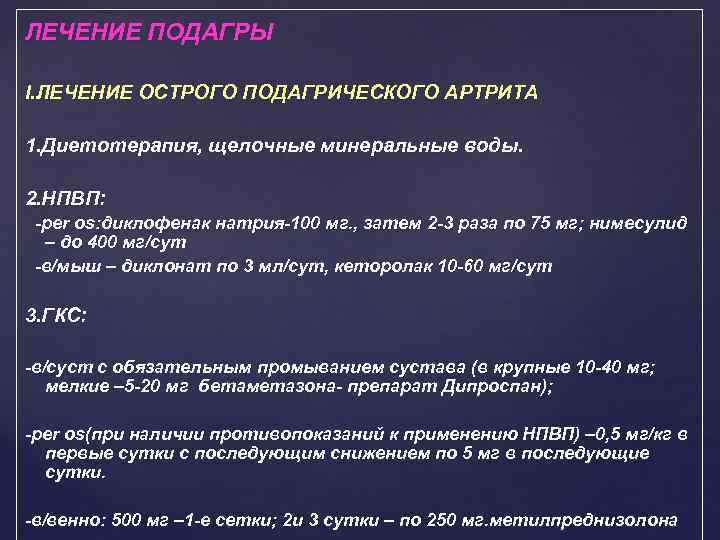

ЛЕЧЕНИЕ ПОДАГРЫ I. ЛЕЧЕНИЕ ОСТРОГО ПОДАГРИЧЕСКОГО АРТРИТА 1. Диетотерапия, щелочные минеральные воды. 2. НПВП: -рer os: диклофенак натрия-100 мг. , затем 2 -3 раза по 75 мг; нимесулид – до 400 мг/сут -в/мыш – диклонат по 3 мл/сут, кеторолак 10 -60 мг/сут 3. ГКС: -в/суст с обязательным промыванием сустава (в крупные 10 -40 мг; мелкие – 5 -20 мг бетаметазона- препарат Дипроспан); -реr os(при наличии противопоказаний к применению НПВП) – 0, 5 мг/кг в первые сутки с последующим снижением по 5 мг в последующие сутки. -в/венно: 500 мг – 1 -е сетки; 2 и 3 сутки – по 250 мг. метилпреднизолона

ЛЕЧЕНИЕ ПОДАГРЫ I. ЛЕЧЕНИЕ ОСТРОГО ПОДАГРИЧЕСКОГО АРТРИТА 1. Диетотерапия, щелочные минеральные воды. 2. НПВП: -рer os: диклофенак натрия-100 мг. , затем 2 -3 раза по 75 мг; нимесулид – до 400 мг/сут -в/мыш – диклонат по 3 мл/сут, кеторолак 10 -60 мг/сут 3. ГКС: -в/суст с обязательным промыванием сустава (в крупные 10 -40 мг; мелкие – 5 -20 мг бетаметазона- препарат Дипроспан); -реr os(при наличии противопоказаний к применению НПВП) – 0, 5 мг/кг в первые сутки с последующим снижением по 5 мг в последующие сутки. -в/венно: 500 мг – 1 -е сетки; 2 и 3 сутки – по 250 мг. метилпреднизолона